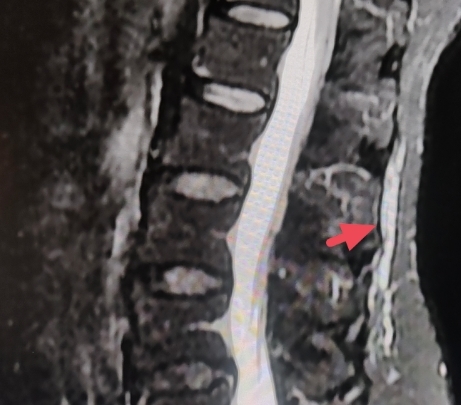

4、手术治疗,对各种非手术治疗无效的病例,可施行手术治疗.

5、激光针刀松解术